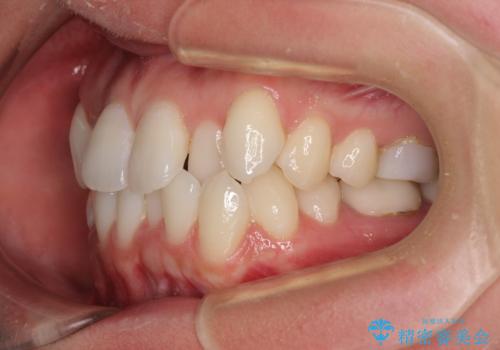

- 2、3年後にワーキングホリデーで海外に行くため、その前に歯列やむし歯をきれいにしたいとのことで来院された患者様です。

抜歯の必要な右上の奥歯は事前に抜歯をし、インビザラインにて上下歯列を整えることとしました。

矯正治療後半に奥歯の補綴治療が必要な歯にはオールセラミッククラウンを装着し、インビザラインで最終的に仕上げることとしました。

海外に行く前に口腔内環境を整えることができ、患者様には大変満足していただきました。